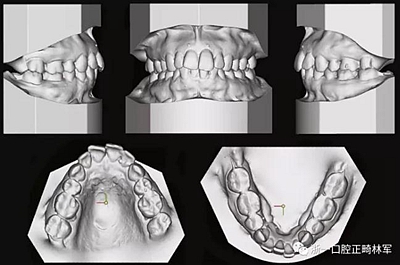

患者曾行正畸治療,現(xiàn)覺(jué)笑容不美觀前來(lái)就診。患者正面觀及側(cè)貌示下頜發(fā)育不足,偏高角,唇閉合不全。上下頜中線齊。覆合、覆蓋4毫米。磨牙關(guān)系及尖牙關(guān)系II類(lèi)。上頜擁擠度4mm,下頜擁擠度6mm。4顆第一前磨牙在第一次正畸治療時(shí)已拔除。上下牙弓呈尖圓型,牙弓狹窄。

因此最終,我們決定采用手術(shù)輔助快速擴(kuò)弓進(jìn)行上下頜擴(kuò)弓,上頜行腭中縫切開(kāi)術(shù)、下頜行正中劈開(kāi)后使用hyrax擴(kuò)弓器進(jìn)行擴(kuò)弓。擴(kuò)弓完成后再使用固定矯治器進(jìn)行矯正。

由于下頜中切牙間沒(méi)有間隙行下頜正中切開(kāi)術(shù),故進(jìn)行術(shù)前正畸擴(kuò)展間隙。下頜前牙粘托槽,中切牙托槽成交放置,將中切牙牙根分開(kāi)。使用0.018X0.018鎳鈦絲及置于下頜左、右中切牙之間的推簧推間隙。3個(gè)月后拍攝CBCT示已有足夠間隙行下頜正中截骨術(shù)。

全麻下進(jìn)行上頜骨腭中縫骨皮質(zhì)劈開(kāi)及下頜正中劈開(kāi)術(shù)。手術(shù)后,用X光片檢查上頜骨和下頜骨中線切口的位置和方向。

患者側(cè)貌改善,下唇唇肌緊張消失,上下唇可自然閉合。磨牙及尖牙關(guān)系糾正至I類(lèi),覆合覆蓋正常。上下頜弓型糾正至卵圓形,牙弓寬度增加。頭影測(cè)量分析示SNA角81.8°,ANB角3°。頭影測(cè)量重疊圖示下頜骨向后旋轉(zhuǎn),垂直面高度略有增加。